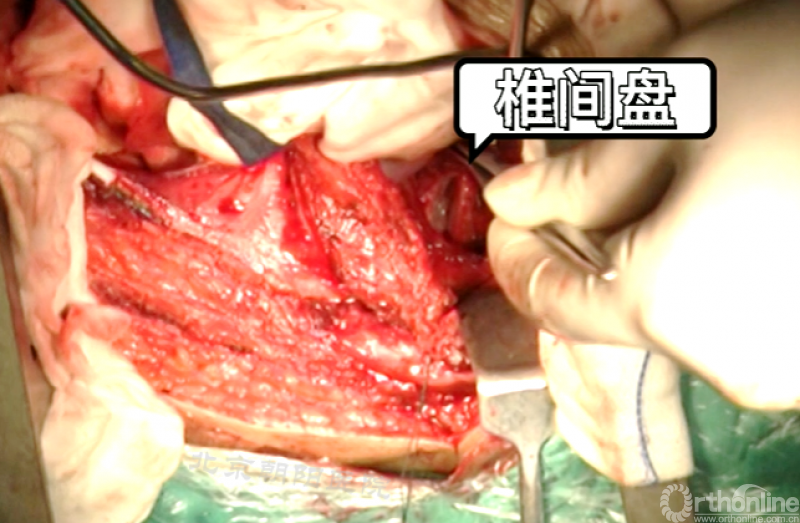

切开纤维环,去除终板椎间盘组织,直至纤维环的后侧边缘,对于严重侧凸如果需要可至后纵韧带。

进一步使用刮匙和髓核钳完整去除椎间盘组织和终板,营造植骨面。